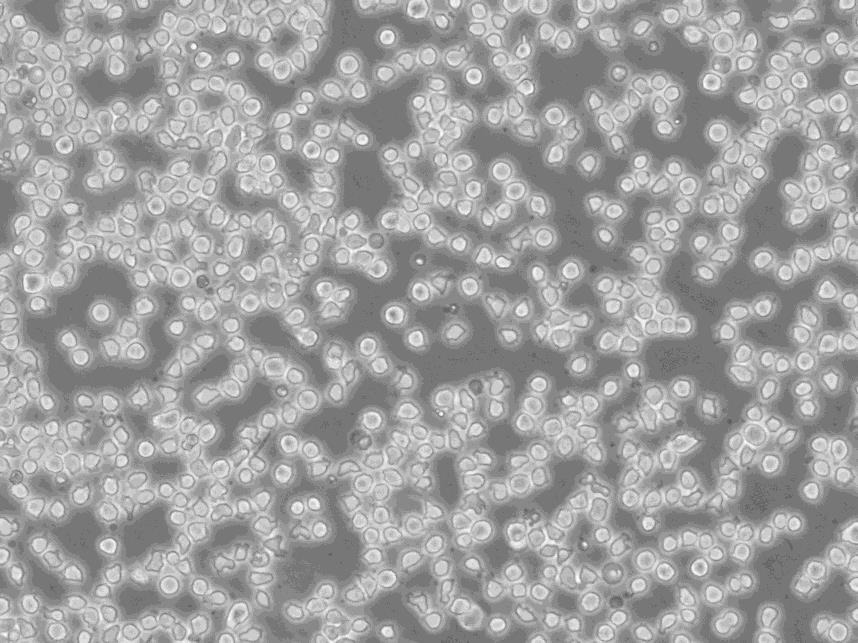

细胞形态:淋巴母细胞样

细胞生长:悬浮

细胞背景资料:急性髓系白血病;男性

细胞生长特性:悬浮